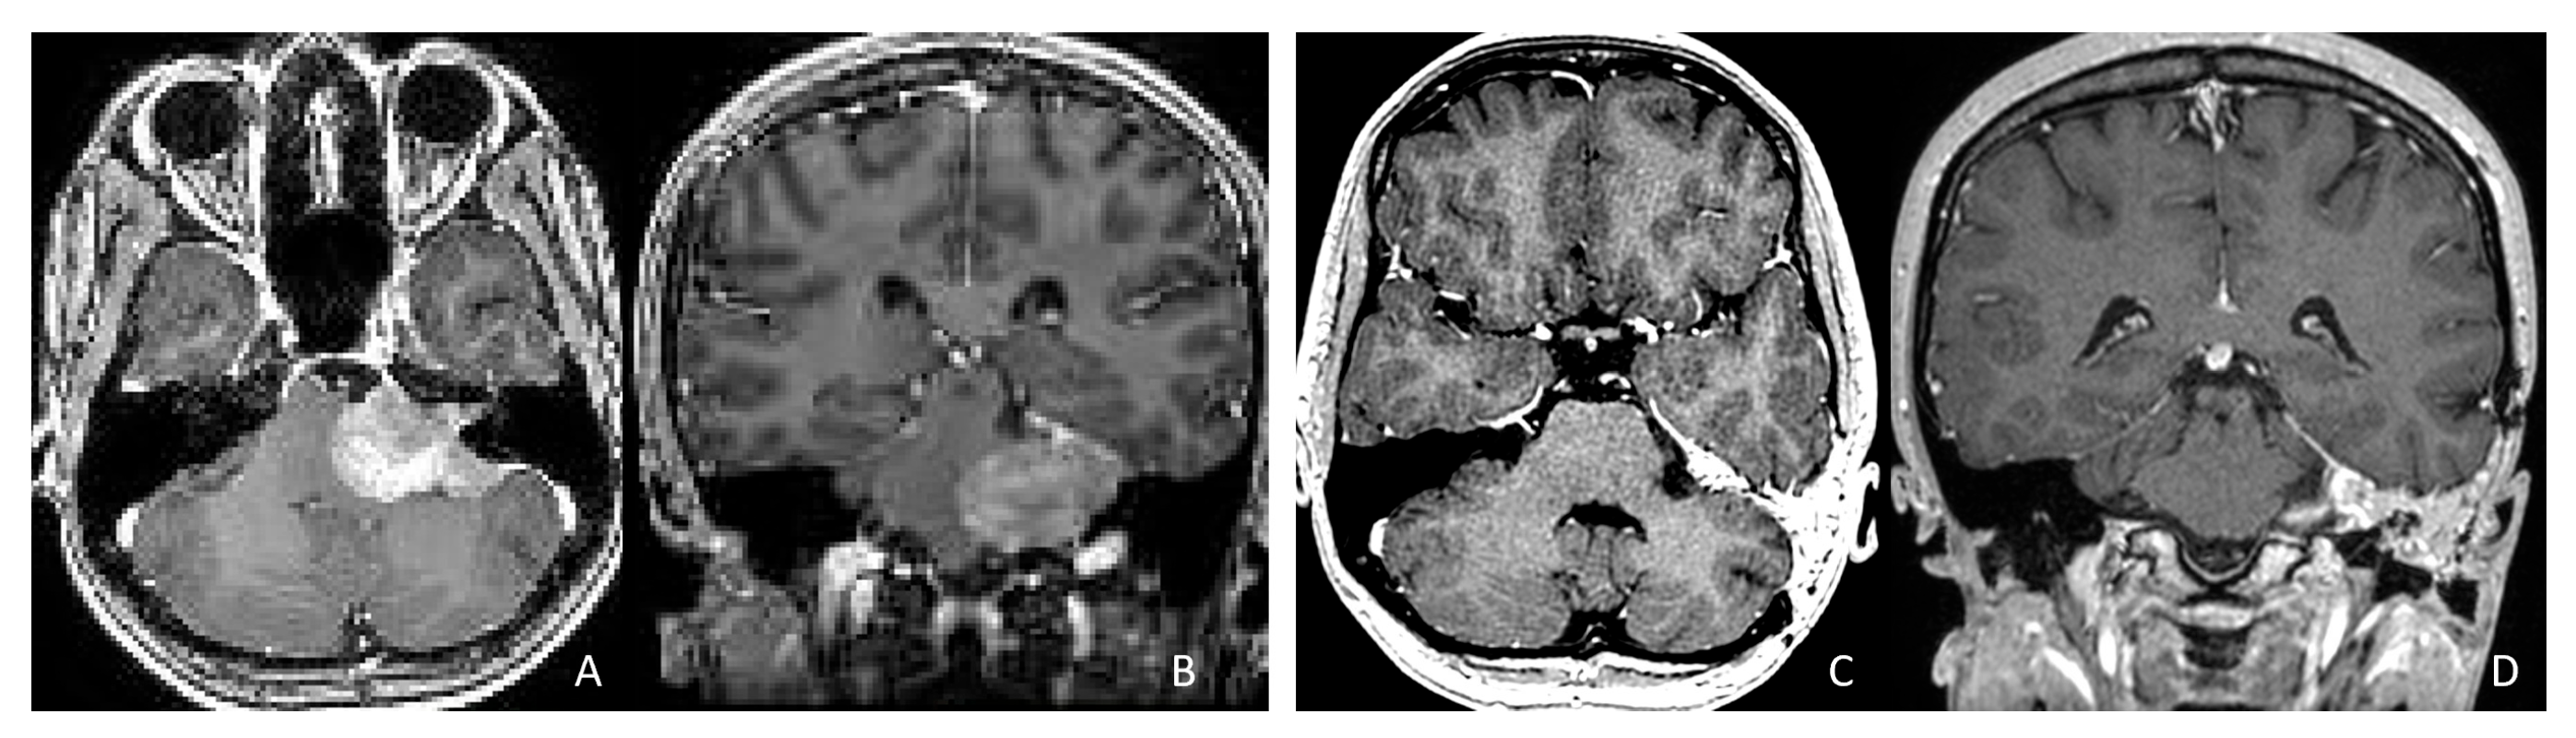

Figure 12.

CPA ATRT. (A–D): MR images ((A): axial; (B): coronal) of a 20-year-old girl, the oldest in this cohort, who presented with left-sided hearing loss and partial facial weakness, reveal ATRT that appears to originate from the vestibular nerve. Surgical findings and post-resection MR images ((C): axial; (D): coronal) indicate no tumor invasion into the cerebellum or brainstem, which contrasts with typical presentations of infantile ATRT.